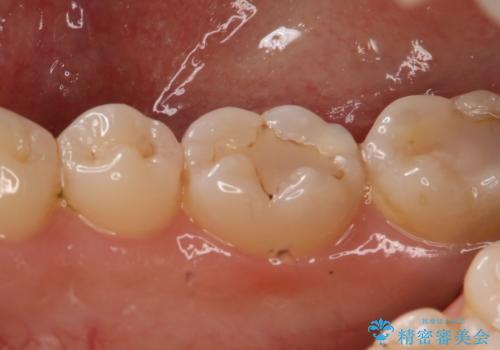

- 右下大臼歯の保険材料劣化に伴う虫歯の治療を希望された患者さまです。

審美性や精度の高い治療を希望されたので切削量や形態を考慮し、セラミックインレーでの治療を選択しました。

保険治療で使用される材料は劣化しやすく直下で虫歯が進行していることが多いです。

今回の患者さまは遠心部の虫歯が深かったのでCRで裏層した上で形成・印象を行いインレーセットを行っています。